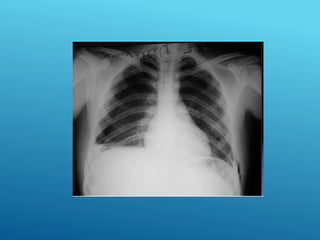

HEMOTÓRAX DERECHO

HEMONEUMOtórax

24/03/2017